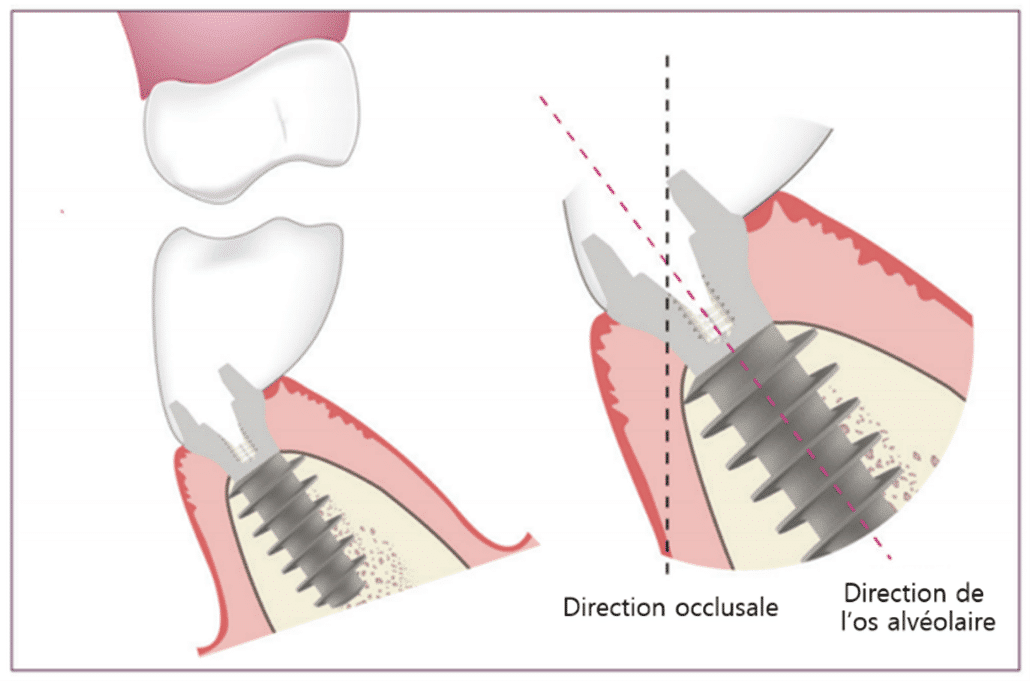

Le Magic Post est une structure située au sommet du MagiCore. Il améliore la polyvalence des prothèses des implants de niveau tissulaire et permet une implantation au centre de l’os de la mâchoire (ostéo-centrée).

Lors de l’installation d’un implant bone level en deux parties au niveau de l’os avec la connexion interne largement utilisée, il est nécessaire d’aligner la direction des forces occlusales avec l’axe longitudinal de l’implant afin d’éviter les fractures de l’implant. Dans certains cas, pour aligner ces deux directions, une intervention chirurgicale plus invasive au niveau de la prothèse peut être nécessaire pour adapter la forme finale de la prothèse.

En revanche, le MagiCore évite le désalignement de la prothèse, même dans les situations où il existe une grande différence entre la direction des forces occlusales et l’axe longitudinal de l’implant, grâce à la double connexion solide fournie par le Magic Post (figures 13, 14).

(Figures 13) Utilisation du MagiCore dans les cas où il y a une importante disparité entre la direction des forces occlusales et l’axe longitudinal de l’implant lors de sa pose.

(Figures 14) Utilisation du MagiCore dans les cas où il y a une importante disparité entre la direction des forces occlusales et l’axe longitudinal de l’implant lors de sa pose.

De plus, grâce aux caractéristiques du Magic Fin Thread mentionnées précédemment, il peut augmenter la résistance aux forces de cisaillement.